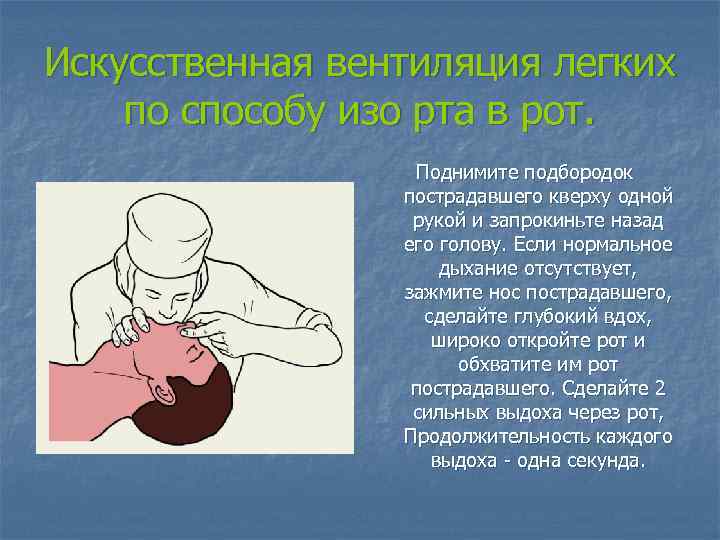

Искусственная вентиляция легких по способу изо рта в рот. Поднимите подбородок пострадавшего кверху одной рукой и запрокиньте назад его голову. Если нормальное дыхание отсутствует, зажмите нос пострадавшего, сделайте глубокий вдох, широко откройте рот и обхватите им рот пострадавшего. Сделайте 2 сильных выдоха через рот, Продолжительность каждого выдоха - одна секунда.